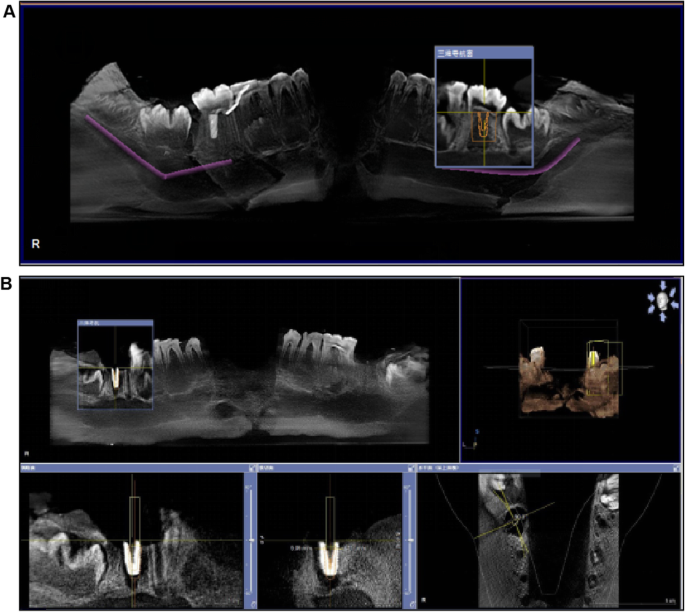

Preparation before examination

The mandible of a pig (Yorkshire) was scanned using cone-beam computed tomography (CBCT). The imagine data were imported into a software (Sirona Dental, GALILEOS Viewer, German). According to the bone condition and anatomical structure, the best implantation site on the mandibular second molar was designed by the teachers (Fig. 3a). Subsequently, the ideal site was assessed for deviation from the actual site (Fig. 3b).

Implant accuracy

The CBCT scan of the implanted site and the imported data were used to evaluate the rationality of implanting in order to calculate the angular, apical, and shoulder deviations. (Fig. 4).